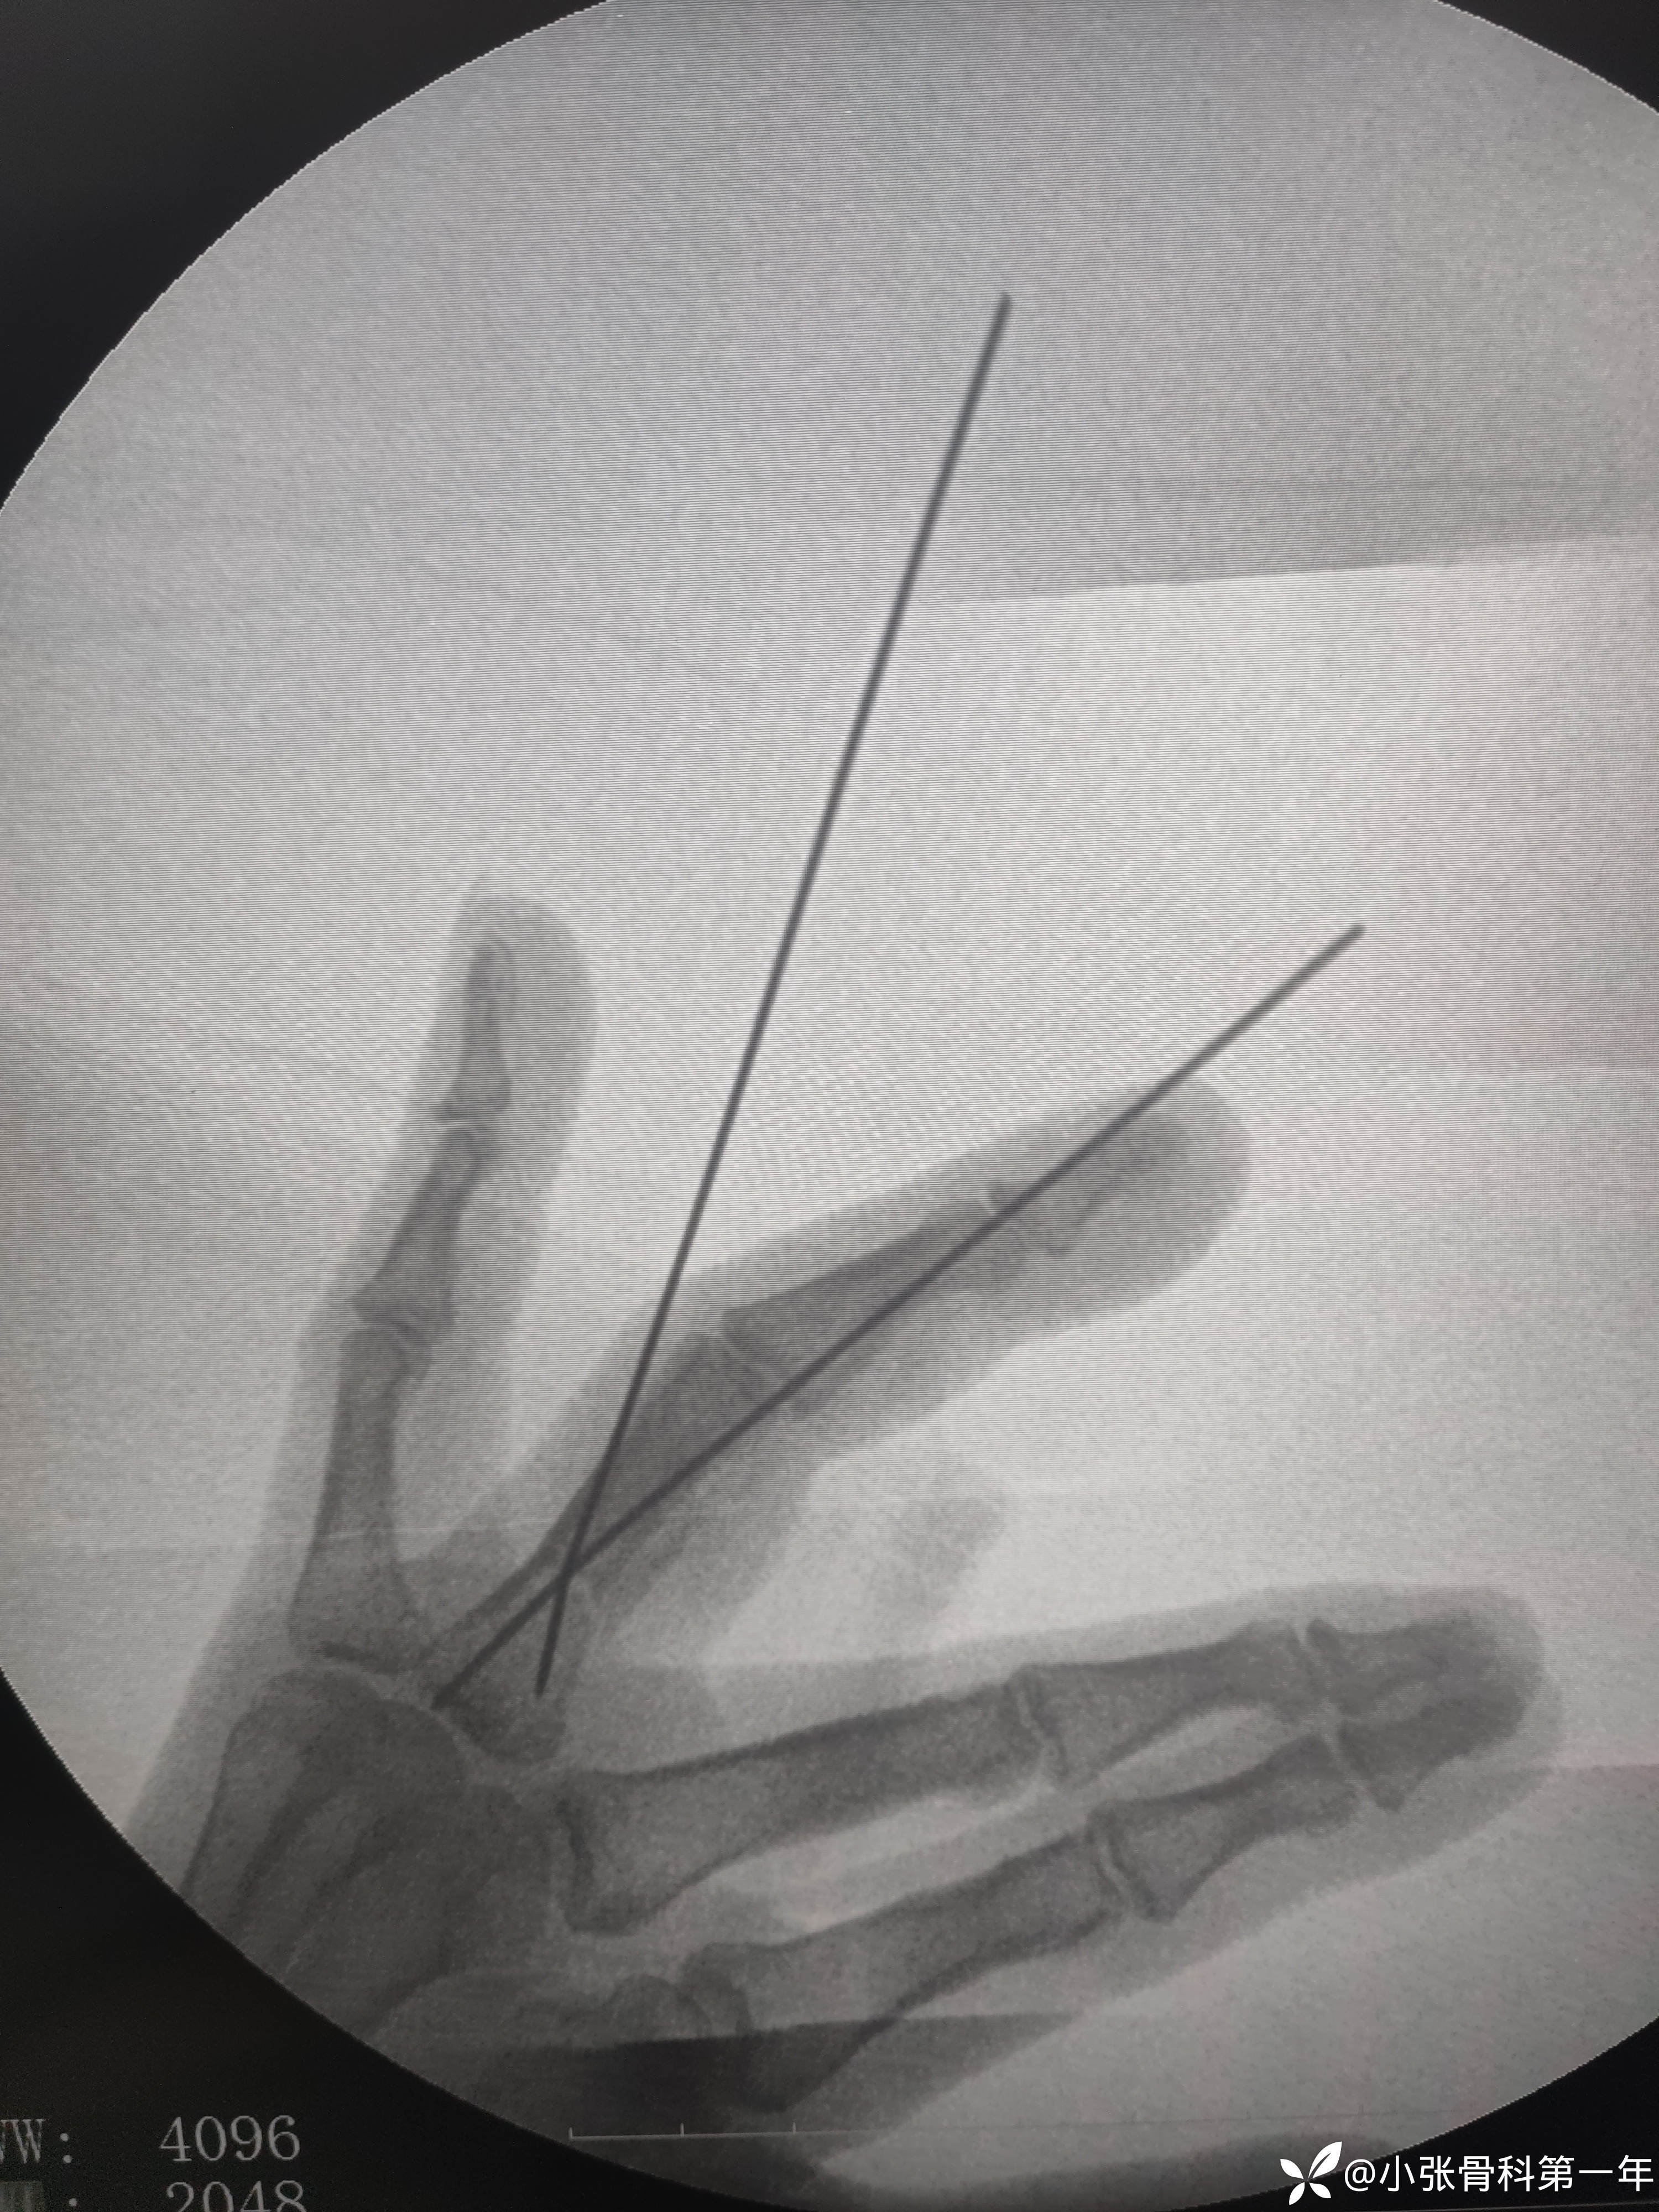

急诊闭合复位克氏针内固定术

用2枚1.2克氏针,第二枚打架,一直过不去,调整角度位置不好,最后换了1.0的一枚,吸取教训了,耽误了半个小时,手术下来心情沉重,以为半小时就ok了,吃一堑长一智。

有老师指骨骨折闭合复位技巧跟克氏针选取指导一下,想学张三版主的克氏针外架,但是心里还是选了传统的交叉克氏针。